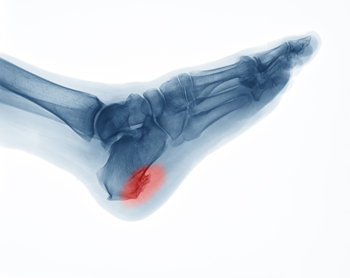

Causes and Risks of Heel Spurs

Heel spurs are bony protrusions on the underside of the heel bone that in some cases can cause discomfort and pain. It is generally believed that heel spurs form when calcium deposits accumulate over several months on the calcaneus, or heel bone. However, heel spurs can also be associated with other foot issues, such as plantar fasciitis, where inflammation of the tissue under the foot can contribute to their development. In addition, certain medical conditions like gout, rheumatoid arthritis, and ankylosing spondylitis, all of which damage the joints, can result in heel spurs. Risk factors of heel spurs include having flat feet, engaging in high-impact aerobic exercises, and aging, particularly among people over 62 years old. Obesity, overpronation, and wearing high heels can significantly raise the risk of heel spur development. In fact, younger women tend to have a higher incidence of heel spurs, possibly due to the use of high heels, which can impact foot biomechanics. If you're experiencing heel pain, especially if it's persistent, it's suggested that you make an appointment with a podiatrist for a proper diagnosis and tailored treatment plan.

Heels Spurs

Heel spurs are formed by calcium deposits on the back of the foot where the heel is. This can also be caused by small fragments of bone breaking off one section of the foot, attaching onto the back of the foot. Heel spurs can also be bone growth on the back of the foot and may grow in the direction of the arch of the foot.

Older individuals usually suffer from heel spurs and pain sometimes intensifies with age. One of the main condition's spurs are related to is plantar fasciitis.

Pain

The pain associated with spurs is often because of weight placed on the feet. When someone is walking, their entire weight is concentrated on the feet. Bone spurs then have the tendency to affect other bones and tissues around the foot. As the pain continues, the feet will become tender and sensitive over time.

Treatments

There are many ways to treat heel spurs. If one is suffering from heel spurs in conjunction with pain, there are several methods for healing. Medication, surgery, and herbal care are some options.